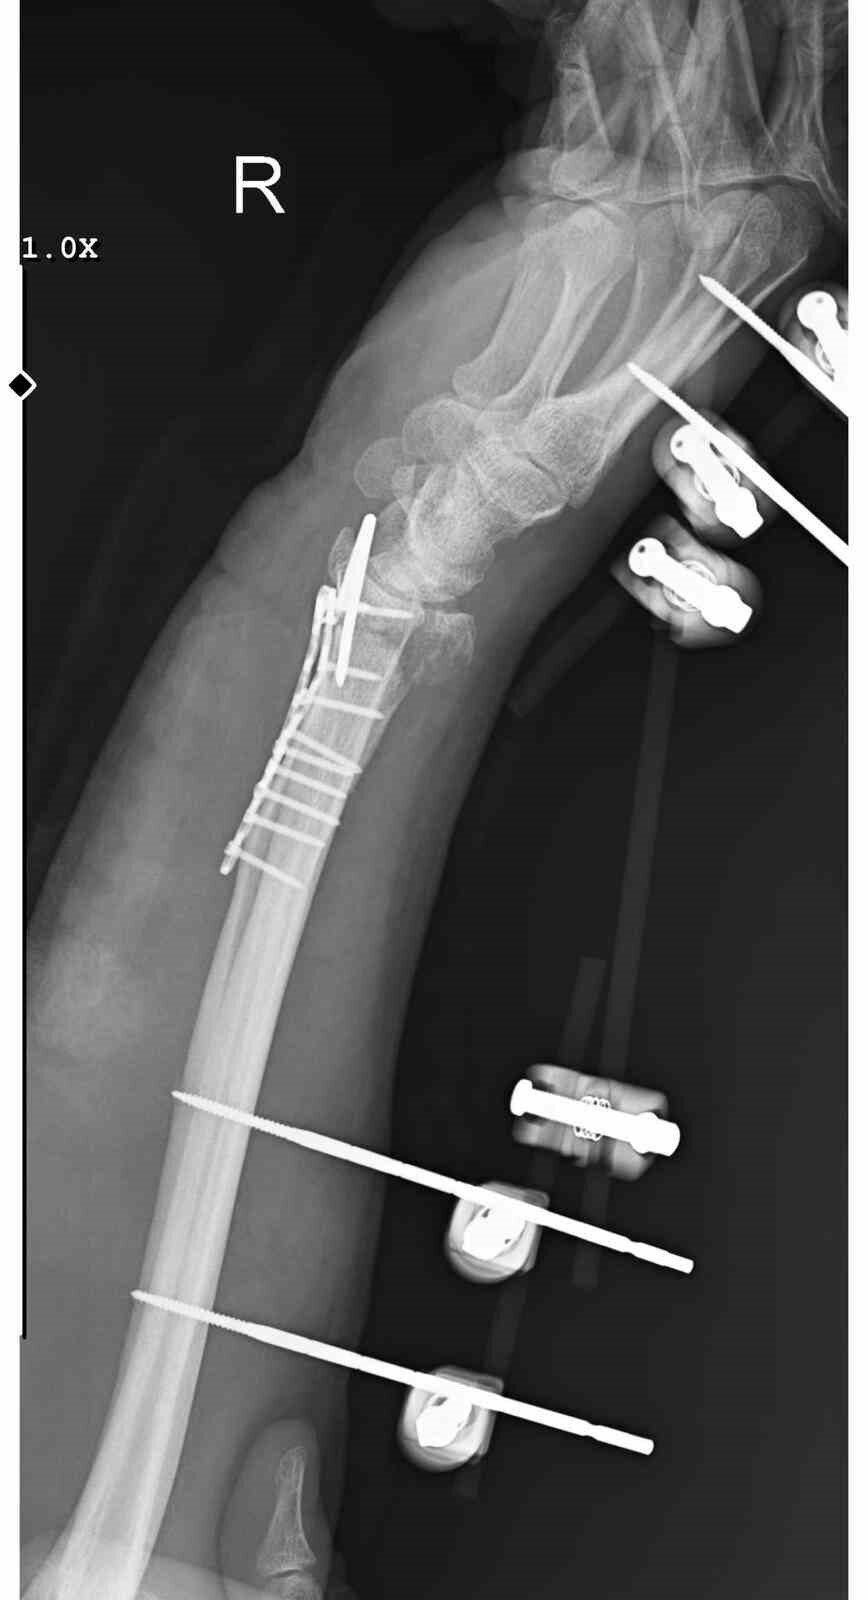

Olay, 29 Aralık günü Mamak’ta gerçekleşti. Alınan bilgilere göre, 35 yaşındaki Yasin Arslantaş, yaşadığı apartmanın önünde yaklaşık 10 sahipsiz köpek tarafından kovalandı. Kaçmaya çalışırken düşerek el bileğini kıran Arslantaş, ambulansla hastaneye kaldırıldı. Bilek kemiğine 11 adet platin takılan Arslantaş’ın kolunda kalıcı his ve hareket kaybı yaşandı. Olay nedeniyle maddi ve manevi açıdan zor günler geçirdiğini belirten Arslantaş, belediye ekiplerinin yaşanan probleme hala çözüm üretmediğini iddia etti.

Bileğimde 15 dikiş ve 11 platin var

Yasin Arslantaş, “Sabah apartmandan çıkış yaptığım sırada arkamdan 9 köpeğin geldiğini gördüm. Saldırgan hale gelmişlerdi. Bana saldırmak üzerelerdi. Kaçmaya çalışırken ayağım kaydı ve düştüm. Bileğimde 15 dikiş ve 11 platin var. İki ay boyunca kolum bu halde kalacak, ardından da 2 buçuk ay fizik tedavi süreci olacak. Doktorlar his ve hareket kaybımın olacağını söylediler. Bileğimde büyük kemiğin kırılmasından dolayı zorlu bir süreç geçiriyorum. 3 saatlik bir ameliyat geçirdim” dedi.